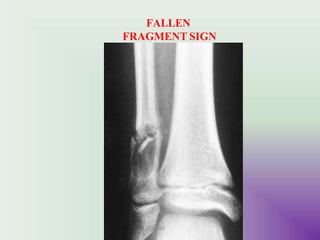

FALLEN FRAGMENT SIGN - # fragment in the cyst

FALLEN

FRAGMENT SIGN

UMY

Bone cyst of

humerus

Pathologic fracture

“Falling Fragment Sign”